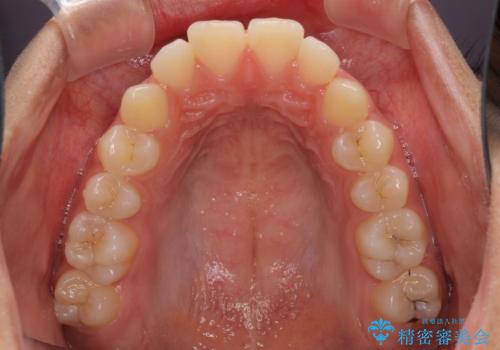

- 上下の出っ歯を気にして来院された患者様です。

口元を積極的に引っ込めるために、上下左右の第一小臼歯を4本抜歯することとしました。

前歯部の突出と開咬は、舌突出癖によるものでしたので、舌のトレーニングをしっかりと行っていただき、1年半程度と短期間で治療を終えることができました。